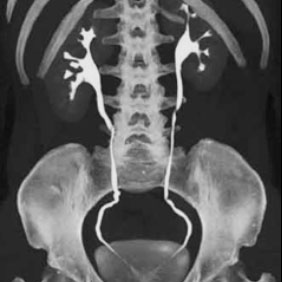

Si no hay ninguna contraindicación, es muy probable que le inyectemos por vena un contraste yodado, que nos aportará una mejor caracterización de los órganos y visualización de las diferentes patologías.